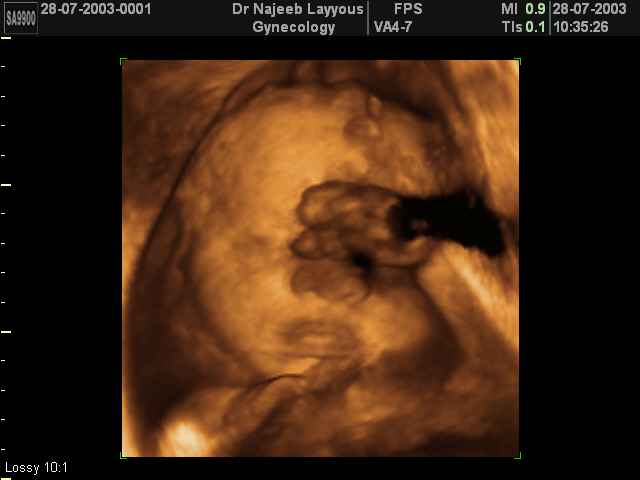

3D Fetal Face Ultrasound Scan Photos